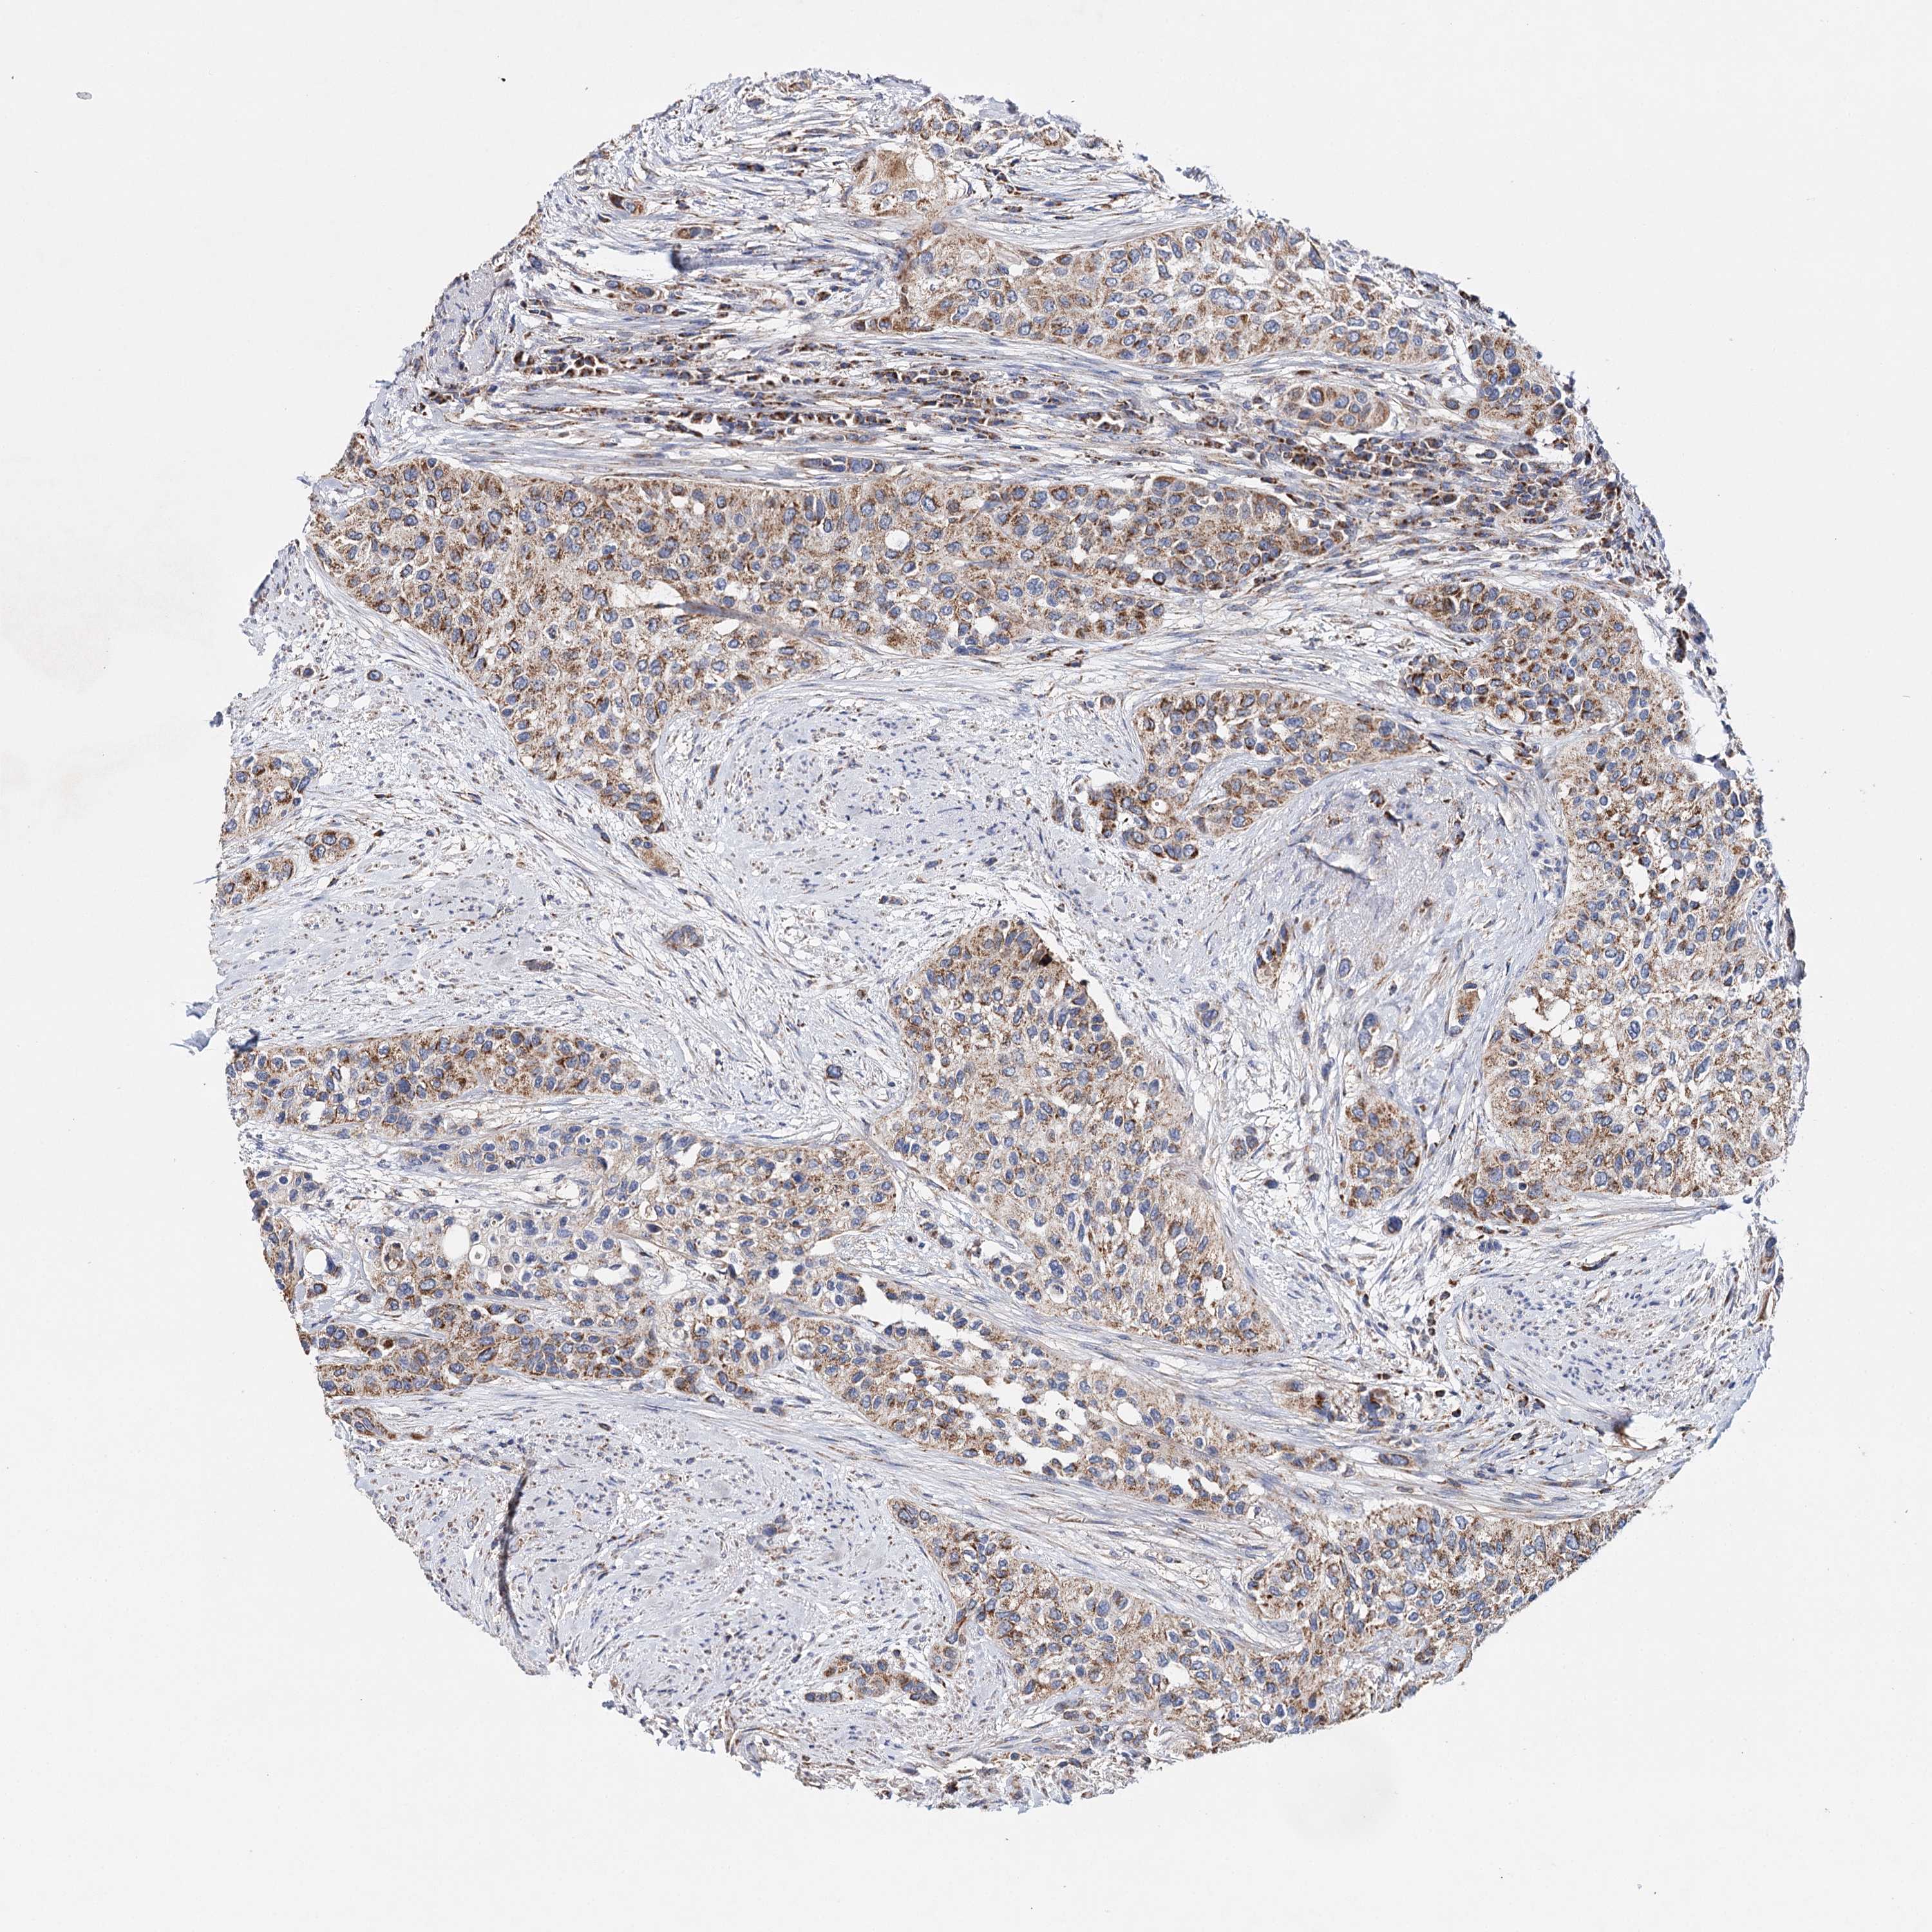

UROTHELIAL CANCER - Protein expressioni

A mouse-over function shows sample information and annotation data. Click on an image to view it in a full screen mode. Samples can be filtered based on level of antibody staining by selecting one or several of the following categories: high, medium, low and not detected. The assay and annotation is described here.

Note that samples used for immunohistochemistry by the Human Protein Atlas do not correspond to samples in the TCGA dataset.

Antibody stainingi

Antibody staining in the annotated cell types in the current human tissue is reported as not detected, low, medium, or high, based on conventional immunohistochemistry profiling in selected tissues. This score is based on the combination of the staining intensity and fraction of stained cells.

Each image is clickable and will lead to virtual microscopy that enables deeper exploration of all samples and also displays staining intensity scores, fraction scores and subcellular localization as well as patient and tissue information for each sample.

Antibody HPA037786

Antibody HPA038034

Antibody HPA038867

Antibody HPA038868

Staining

High

Medium

Low

Not detected

Intensity

Strong

Moderate

Weak

Negative

Quantity

>75%

75%-25%

<25%

None

Location

Nuclear

Cytoplasmic/membranous

Cytoplasmic/membranous,nuclear

Urothelial carcinoma, High grade

Urothelial carcinoma, Low grade

Urothelial carcinoma, NOS